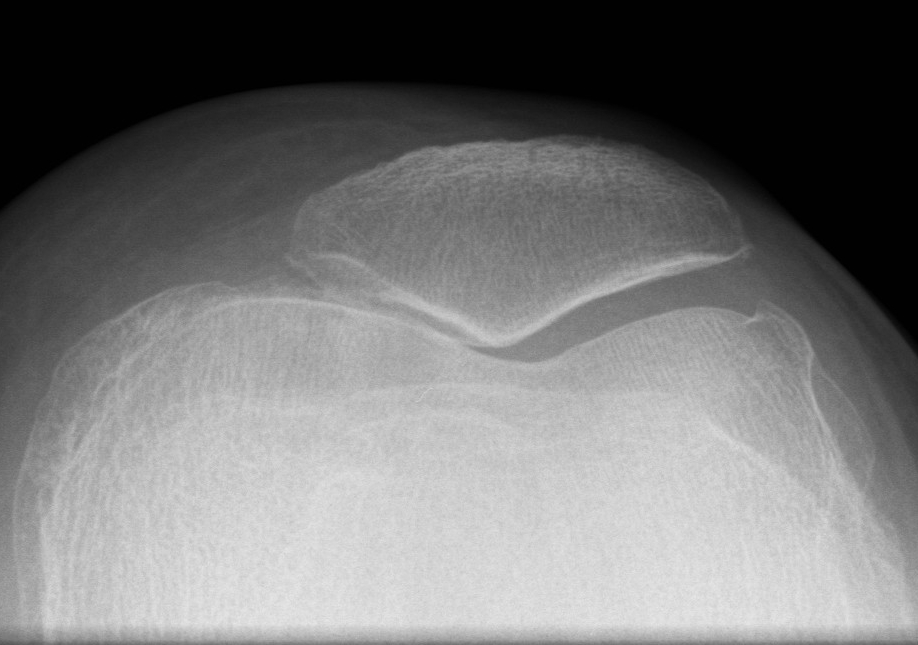

Fat Pad Syndrome

Hoffa's syndrome

- impingement of the fat pad with knee ROM

Diagnosis

Hoffa's sign

- apply pressure to fat pad each side of patella tendon with knee in flexion

- extend knee